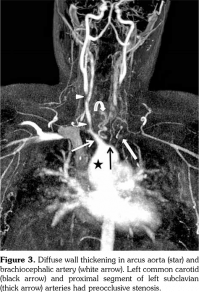

A 14-year-old female patient referred to our clinic with headache and dizziness for two weeks and loss of consciousness for about 10 minutes. On admission, the blood pressure was 90/60 mmHg and all peripheral pulses were palpable. Her body weight was above 97th percentile for her age and body mass index was 33. The fundus examination and other organ systems were essentially normal. Laboratory studies revealed erythrocyte sedimentation rate (ESR) as 108 mm/hour and C-reactive protein (CRP) as 7.5 mg/dL (0-0.8), while other measurements were normal. Urinalysis revealed microscopic hematuria and proteinuria of 31.9 mg/m2/hour in 24-hour urine collection. The cerebrospinal fluid examination showed no abnormalities. Cranial magnetic resonance imaging (MRI) showed multiple millimetric hyperintense deep white matter lesions on T2-weighted imaging (Figure 1). Intracranial and extracranial arteries were normal in magnetic resonance angiography (MRA). Renal biopsy findings were interpreted as FSGS (Figure 2). Patient was considered as cerebral vasculitis and incidental FSGS. Pulse methylprednisolone therapy for three consecutive days was initiated and continued with oral prednisolone. At four years of follow-up, proteinuria decreased to 5-15 mg/m2/hour, and ESR and CRP were normal. Repeated brain MRI and MRA examinations showed no new lesions. Four years later, at the age of 18, on a routine examination, both radial artery pulses were absent and the blood pressure could not be measured. Significant bruit was heard on the left carotid artery. Laboratory studies revealed ESR as 43 mm/hour and CRP as 2.46 mg/dL. Aortic MRA revealed diffuse wall thickening and contrast enhancement in the arcus aorta and its many main branches (Figure 3). Takayasu arteritis diagnosis was established according to the European League Against Rheumatism/ Paediatric Rheumatology International Trials Organisation/Paediatric Rheumatology European Society criteria.[2] Methotrexate was begun, and daily prednisolone was continued. Four months after the diagnosis of TA, left-sided hemiparesis developed. Brain MRI demonstrated a wide cerebral infarct at the right anterior vascular territory (Figure 4). Brain and neck computed tomography angiography showed total occlusion of the right internal carotid artery. Vascular involvement of the right common carotid artery was progressed to preocclusive stenosis. Diameters of the right anterior and middle cerebral arteries were thin and fed by the posterior and anterior communicating arteries (Figure 5). Tocilizumab treatment was started at 8 mg/kg every four weeks. At follow- up with 2.5 years of tocilizumab treatment, the patient's clinical condition improved slightly, and no new symptoms developed. A written informed consent was obtained from the patient.